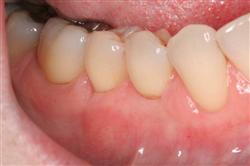

Normally gum tissue surrounds and protects the delicate roots of your teeth. Exposed tooth roots are prone to tooth decay, root canals, discoloration and actual jawbone loss. All of this can lead to tooth loss in advanced cases.

Functional Soft Tissue Grafting replaces the missing gum tissue and protects your teeth. For this reason, soft tissue grafting may be recommended even for back teeth.